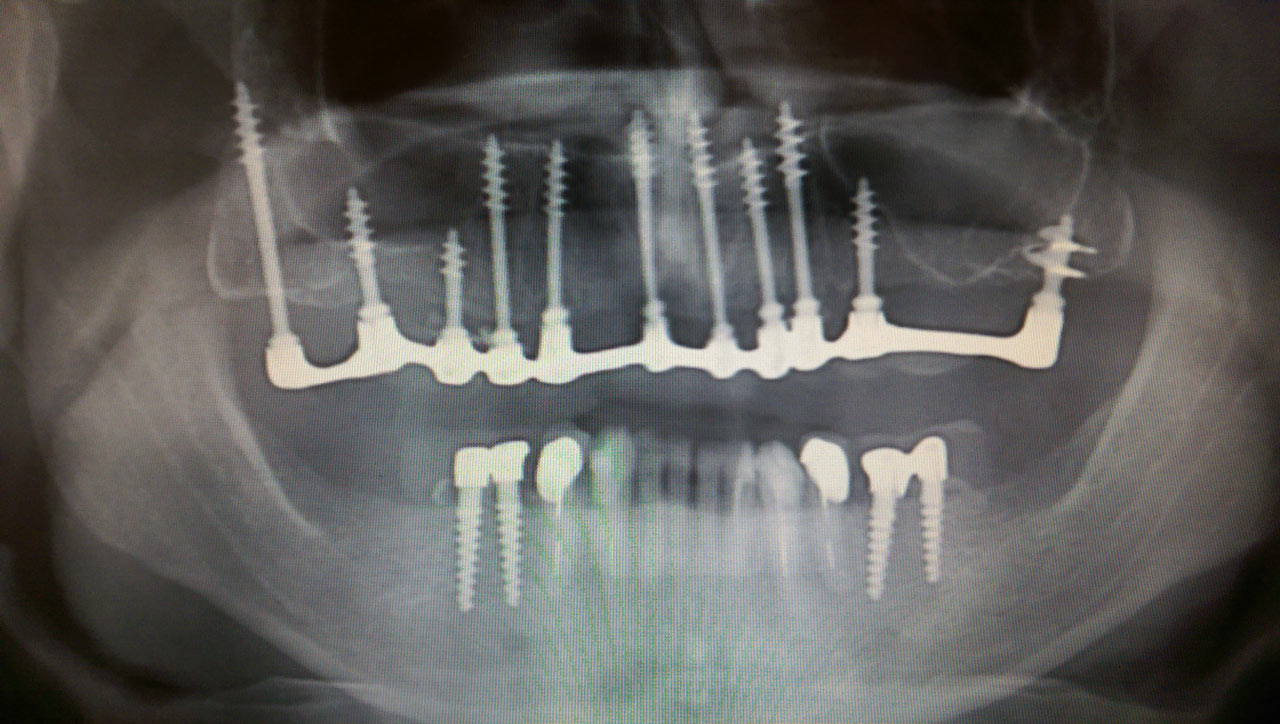

2 nap alatt varázsoltuk ezt a szép esztétikus alsó, felső körhídat implantátumokkal megtámasztva a korábban elhanyagolt szájba. Az 1. nap 26 fogat távolítottunk el, mert annyira rossz állapotban voltak, és rögtön azonnal terhelhető IHDE svájci implantátumokat raktunk be, fentre 8, lentre 6 darabot. A sebeket összevarrtuk és intraorális szkennerrel digitális lenyomatot vettünk. 2 nap múlva pedig beragasztottuk a kész PMMA műanyag körhidakat. Dr. Kelemen Péter és a Symbion Fogtechnika munkája.

Teljes fogatlanság helyreállítása 2 nap alatt azonnal terhelhető svájci IHDE implantátumokkal és PMMA műanyag hidakkal. Intraorális szkennerrel vettünk lenyomatot az implantáció után, és erre a digitális mintára készítette el a fogtechnika a hidak digitális tervezését, majd faragta ki műanyagból. Ezt a gyors munkát az azonnal terhelhető implantátumok és a digitális lenyomat, tervezés segítségével tudtuk megcsinálni mindössze 2 nap alatt. Dr. Kelemen Péter és a Symbion Fogtechnika munkája.

Ismét egy teljes szájüregi rehabilitáció két lépésben. Először az alsó fogak lettek kihúzva és azonnal implantálva, híddal ellátva, majd később a felső. IHDE svájci azonnal terhelhető implantátumok és cirkónium hidak. Dr. Kelemen Péter és a Symbion Fogtechnika közös munkája.